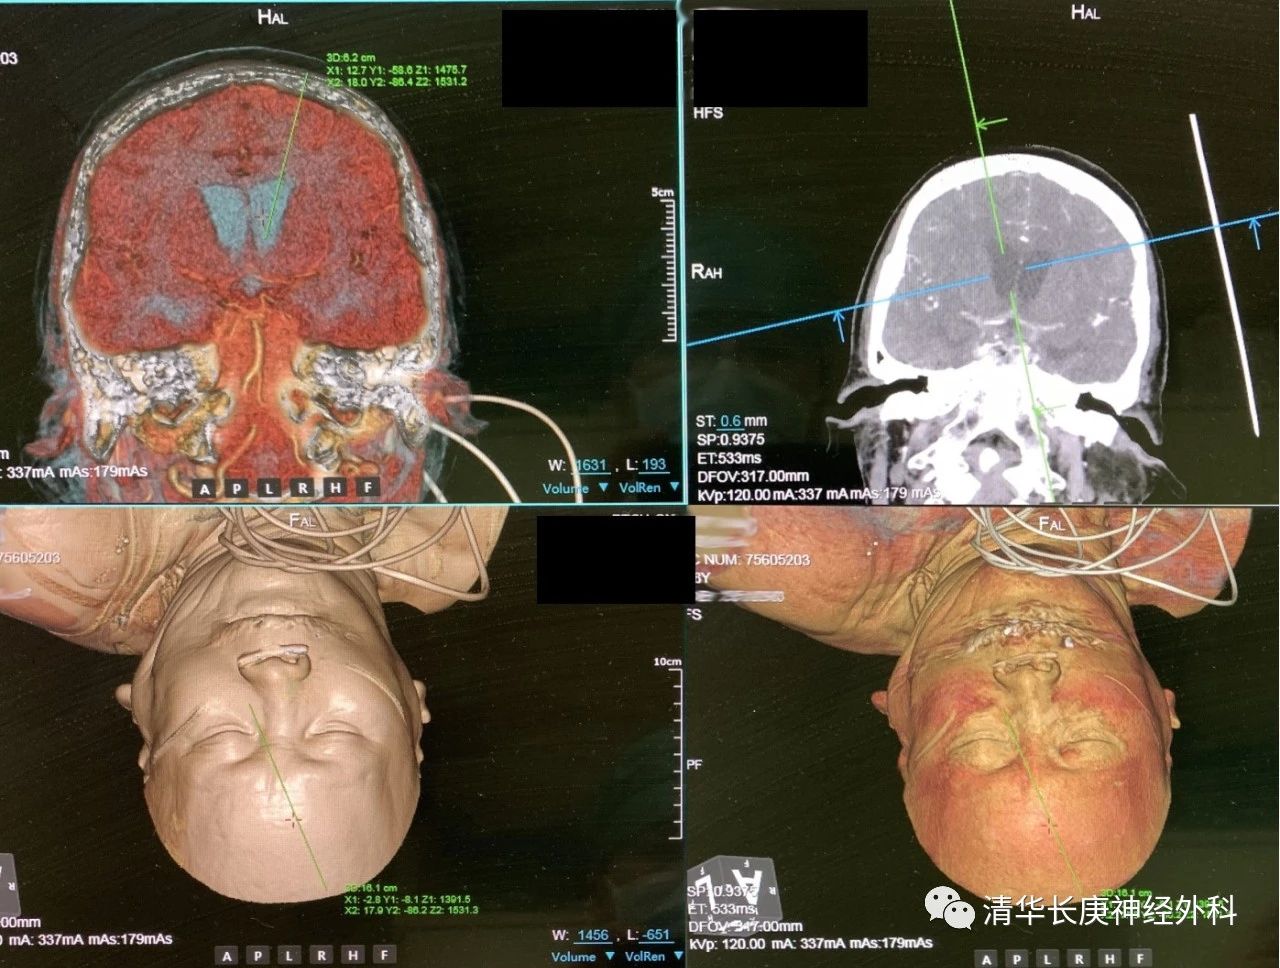

69岁的何女士,4小时前患者突然出现头疼,伴有头晕恶心、呕吐,家人赶紧把她送到医院,头颅CT检查提示“蛛网膜下腔出血”,期间何女士陷入昏迷,呼吸微弱,急诊行气管插管,复查头颅血管CT成像,发现患者又出现了“脑室系统积血、脑积水”,紧急为患者进行了微创脑室穿刺外引流术,术中使用导航引导,确保不损伤功能区脑组织,避开血管,精准到达预定位置,帮助患者排除脑内出血,改善脑积水。患者蛛网膜下腔出血原因尚未明确,先期行脑室及血肿引流,可以减轻症状,待后续病情平稳后再进一步评估,决定后续治疗方案。

图5 三维CT重建,模拟手术穿刺路线

图6 术中导航引导下精准穿刺引流